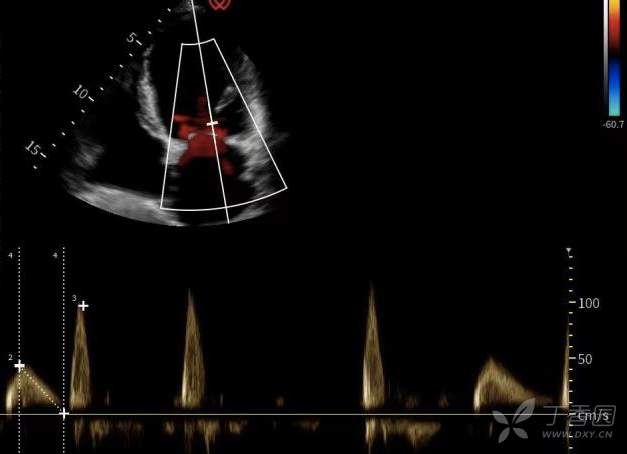

患者胸闷、憋喘症状已明显缓解,超声复查舒张期 E 峰值仅 54.7 cm/s,心房并不存在过高的充盈压,也就是说心衰肺循环淤血应当得到改善,那为什么超声仍提示双肺较多 B 线呢,我们决定进一步完善胸部 CT 评估肺内情况。

超声舒张期 E 峰值 54.7 cm/s。